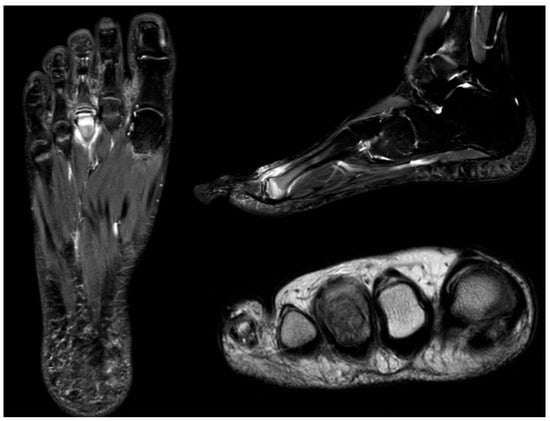

Figure 10.

Radiograph (left) and MRI (right) of a 17-year-old female patient showing necrotic changes and initial flattening of the second metatarsal head.

Figure 11.

Radiograph (left) and MRI (right) of a 15-year-old male patient with osteochondrosis of the third metatarsal head and early signs of deformation.

Figure 12.

MRI of a 12-year-old female patient showing extensive bone marrow edema of the third metatarsal head, consistent with active inflammation and necrosis.